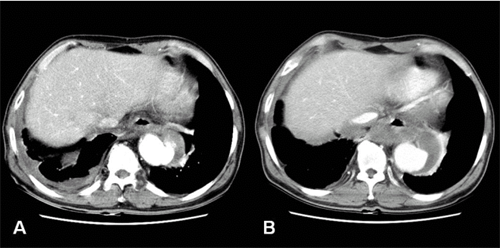

Thoracic aortic dissection Or Aneurysm: Clinical Presentation ...

Thoracic Aortic Dissection or Aneurysm: Clinical Presentation, Diagnostic Imaging and Initial Management in a Tertiary Referral Centre ... Document Retrieval